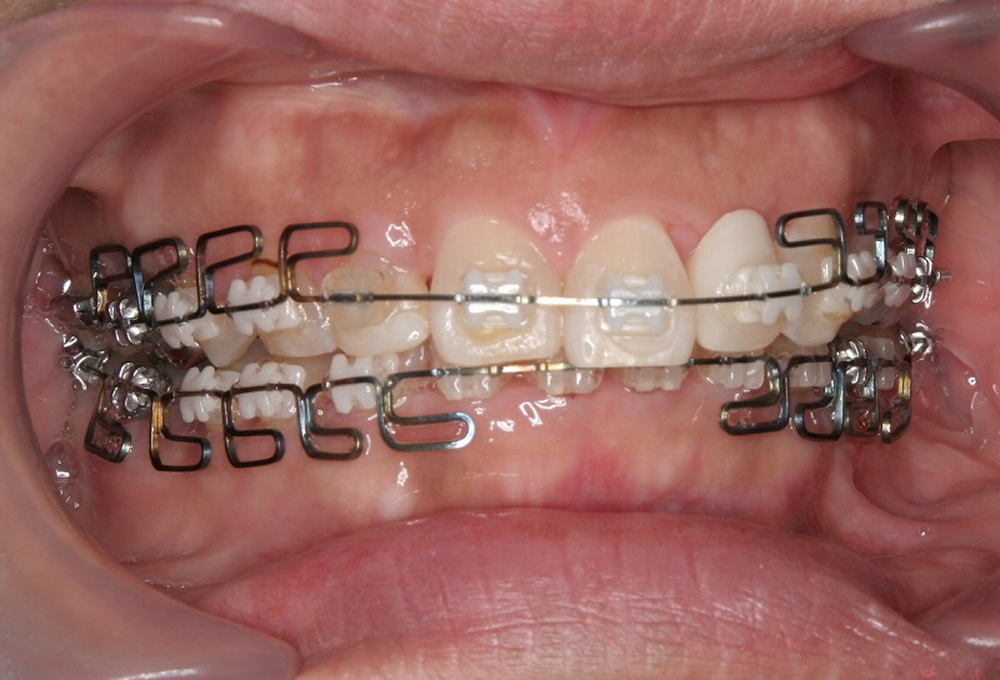

④矯正中